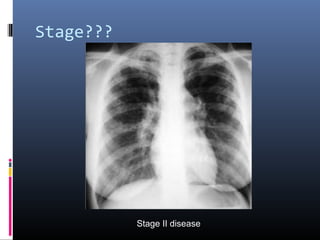

Stage???

Stage II disease

Stage II

• #10 Sarcoidosis, thoracic. Stage II disease. Chest radiograph in a 36-year-old woman shows mediastinal lymph node enlargement and bilateral pulmonary opacities.

• #14 Stage II sarcoidosis. Posteroanterior chest radiograph demonstrates massive bilateral hilar lymphadenopathy as well as bilateral parenchymal infiltrates. Note the predilection for mid and upper lung zones.